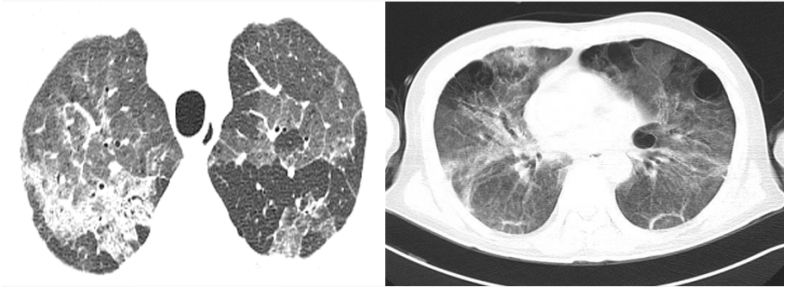

患者,女,50岁;活动后喘息20天,加重伴发热3天,2021年11月19日转入我院。入院胸部CT显示:双肺实变,磨玻璃影(图1)。11月24日复查胸部CT可见病变进展迅速(图2)。予患者气管插管机械通气、俯卧位等,呼吸衰竭未见改善。遂于11月25日启动VV-ECMO(转速2860 rpm,流量4.5 L/min,氧浓度100%)。追问病史:患者入院前1月有活动后气促症状,自觉全身不适,近2年有眼干、口干不适。进一步检查发现,ANA反应阳性(+),ANA核型为胞浆颗粒型(异常);抗SSA/Ro抗体阳性(++)、抗Ro-52抗体阳性(+++)。诊断:急性间质性肺炎(AIP);Ⅰ型呼吸衰竭;混合性结缔组织病。治疗:VV-ECMO+呼吸机辅助通气+俯卧位通气、激素(甲强龙80 mg×7天,60 mg×3天,40 mg qd)、免疫抑制剂(环磷酰胺400 mg qd×3天)、抗感染(哌拉西林他唑巴坦4.5 g q12h+莫西沙星0.4 g qd+氟康唑氯化钠注射液20 mg qd)、抗凝等。在随后的一段时间内,患者影像学改善不明显(图3)。直至12月20日,复查胸部CT可见患者肺部病变较前明显吸收(图4)。2021年12月31日VV-ECMO撤机后,继续气切呼吸机辅助通气,甲强龙40 mg qd抗炎治疗,继续抗感染治疗,2022年1月7日脱机,1月21日气管封管,1月26日出院。后续治疗:强的松25 mg qd,环磷酰胺600 mg q2w×4次,序贯吗替麦考酚酯0.5 g bid。重症间质性肺疾病(ILD)在诊断方面需要考虑以下问题:是ILD吗?是哪种ILD?严重程度如何?在治疗方面,除了生命支持(呼吸支持重点)和病因治疗,并发症的处理也至关重要。重症ILD的诊断包括两方面,一方面是通过影像学、病史+临床表现、BALF-NGS、实验室检查、肺活检等对ILD进行诊断;另一方面涉及重症,患者多面临呼吸衰竭甚至多器官衰竭,因此时间更加紧迫。在ICU内最常见的重症ILD包括:特发性肺纤维化急性加重(AE-IPF)、自身免疫相关性ILD、肿瘤治疗相关性ILD、隐源性机化性肺炎(COP)、AIP、过敏性肺炎(HP)、急性嗜酸性粒细胞性肺炎(AEP)、药物相关ILD等。在影像学方面,最易导致重症的类型有弥漫性磨玻璃影和实变影。最常见的鉴别诊断就是重症肺部感染。表现为弥漫性磨玻璃影或实变影的ILD较为多见,例如:HP、嗜酸性粒细胞性肺炎(EP)、结缔组织病相关间质性肺病(CTD-ILD)、非特异性间质性肺炎(NSIP)、脱屑性间质性肺炎(DIP)、淋巴细胞性间质性肺炎(LIP)、机化性肺炎(OP)、AE-IPF、肺泡蛋白沉积症(PAP)、肺泡微结石症、结节病、弥漫性肺泡出血综合征、肺水肿等。而很多感染性疾病影像学也可表现为磨玻璃影,例如:卡氏肺孢子菌肺炎(PCP)、病毒性肺炎、巨细胞病毒性肺炎、支原体肺炎。尽管如此,ILD也有部分影像学具有特征性,可以被识别。图5左表现为肺陷闭,也称为“猪头肉冻征”,这是典型的亚急性HP的影像学特征。图5右表现为弥漫性磨玻璃影,但以肺门向外扩展,外面有肺大泡,这是典型的PCP表现。临床上多见自身免疫性疾病导致的ILD,此类疾病也具有共同的特征,例如双肺弥漫,病理方面以NSIP或OP为主要特征。但也有部分患者可以出现弥漫性肺泡损伤(DAD)特征。如图6所示,左图为ANCA相关性血管炎,右图为MDA5相关性间质性肺病。因此,一定要警惕容易发生这种病理改变的自身免疫性疾病。